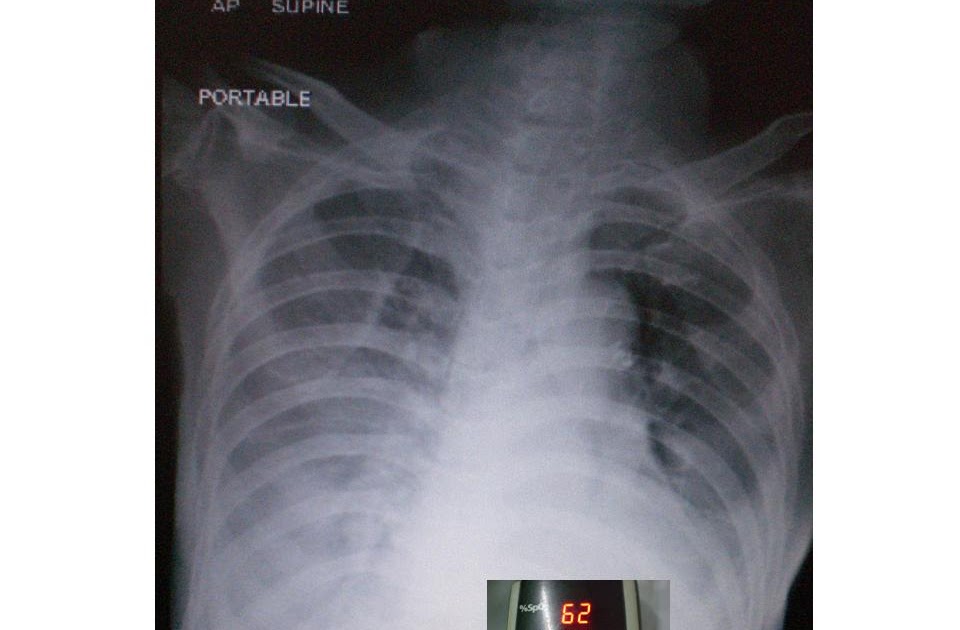

Supine Chest X Ray Pleural Effusion . The larger left effusion produces a hazy increased density in the. Supine chest radiograph reveals large left and small right pleural effusions. Illustration of the chest, depicted in supine position from the lateral aspect, shows a moderate effusion accumulating in the posterior aspect of the chest. Pleural effusions can be caused by many. This layering effusion can be. Fluid in the pleural space initially accumulates in the posterior pleural recess when erect and is not seen on a frontal radiograph until. On supine projections, pleural effusions produce a veiling opacity, which is due to pleural fluid preferentially collecting posteroinferiorly in the.

Fluid in the pleural space initially accumulates in the posterior pleural recess when erect and is not seen on a frontal radiograph until. On supine projections, pleural effusions produce a veiling opacity, which is due to pleural fluid preferentially collecting posteroinferiorly in the. Supine chest radiograph reveals large left and small right pleural effusions. The larger left effusion produces a hazy increased density in the. This layering effusion can be. Pleural effusions can be caused by many. Illustration of the chest, depicted in supine position from the lateral aspect, shows a moderate effusion accumulating in the posterior aspect of the chest.